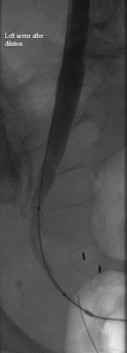

Distal left ureter after dilation

Published July 12, 2014 at 127 × 353 in Bilateral insertion of nephroureteral stents after balloon dilation of malignant obstruction of the distal ureters. Ken U. Ekechukwu, MD, MPH, FACP..